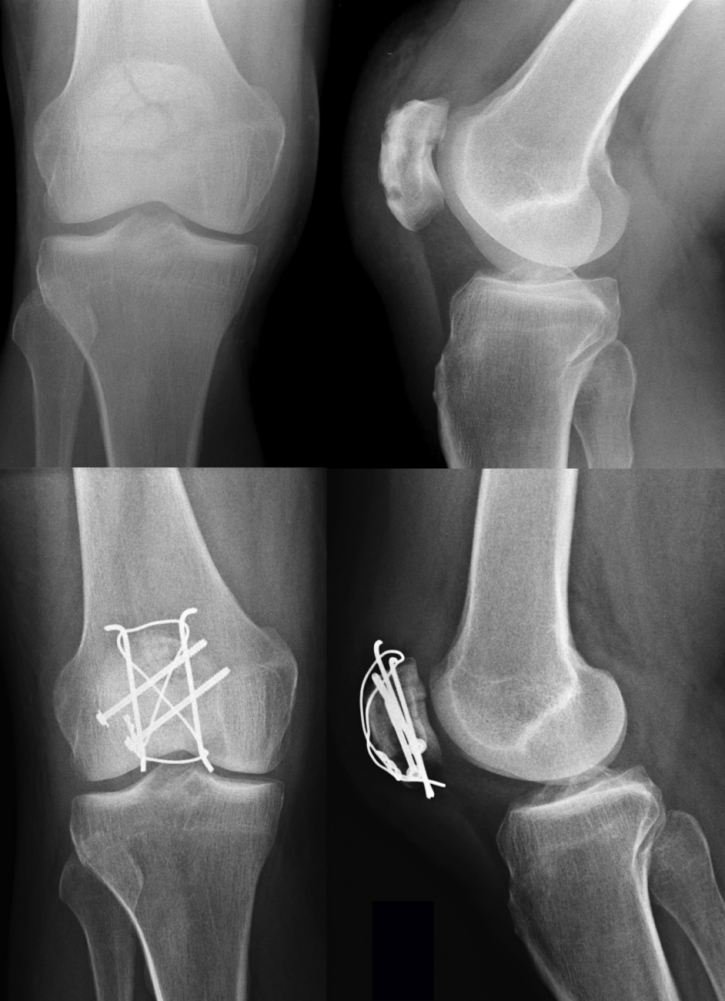

As previously mentioned, every unstable fracture of the patella requires operative intervention. The modified tension band wiring, according to AO principles, is the most accepted and widely used technique for the treatment of displaced fractures of the patella, although several other techniques involving combinations of fixation techniques (i.e. K-wires, screws and cerclage wiring; Figure 3 [Fig. 3]) have been published [8], [60]. From a biomechanical point of view, the surgical procedure aims to neutralize tension forces applied to the patella via the extensor mechanism and convert them into compression forces. For this purpose, at least two K-wires are placed perpendicular to the fracture line and a tension band is applied in an eight-shaped manner to secure reduction. The ends of the K-wires are then twisted and buried in the patella.

Figure 3: Preoperative X-rays of a comminuted patella fracture (above). 3 months post-surgery using a combination out of K-wires, screws, and an eight-shaped cerclage wiring (below).